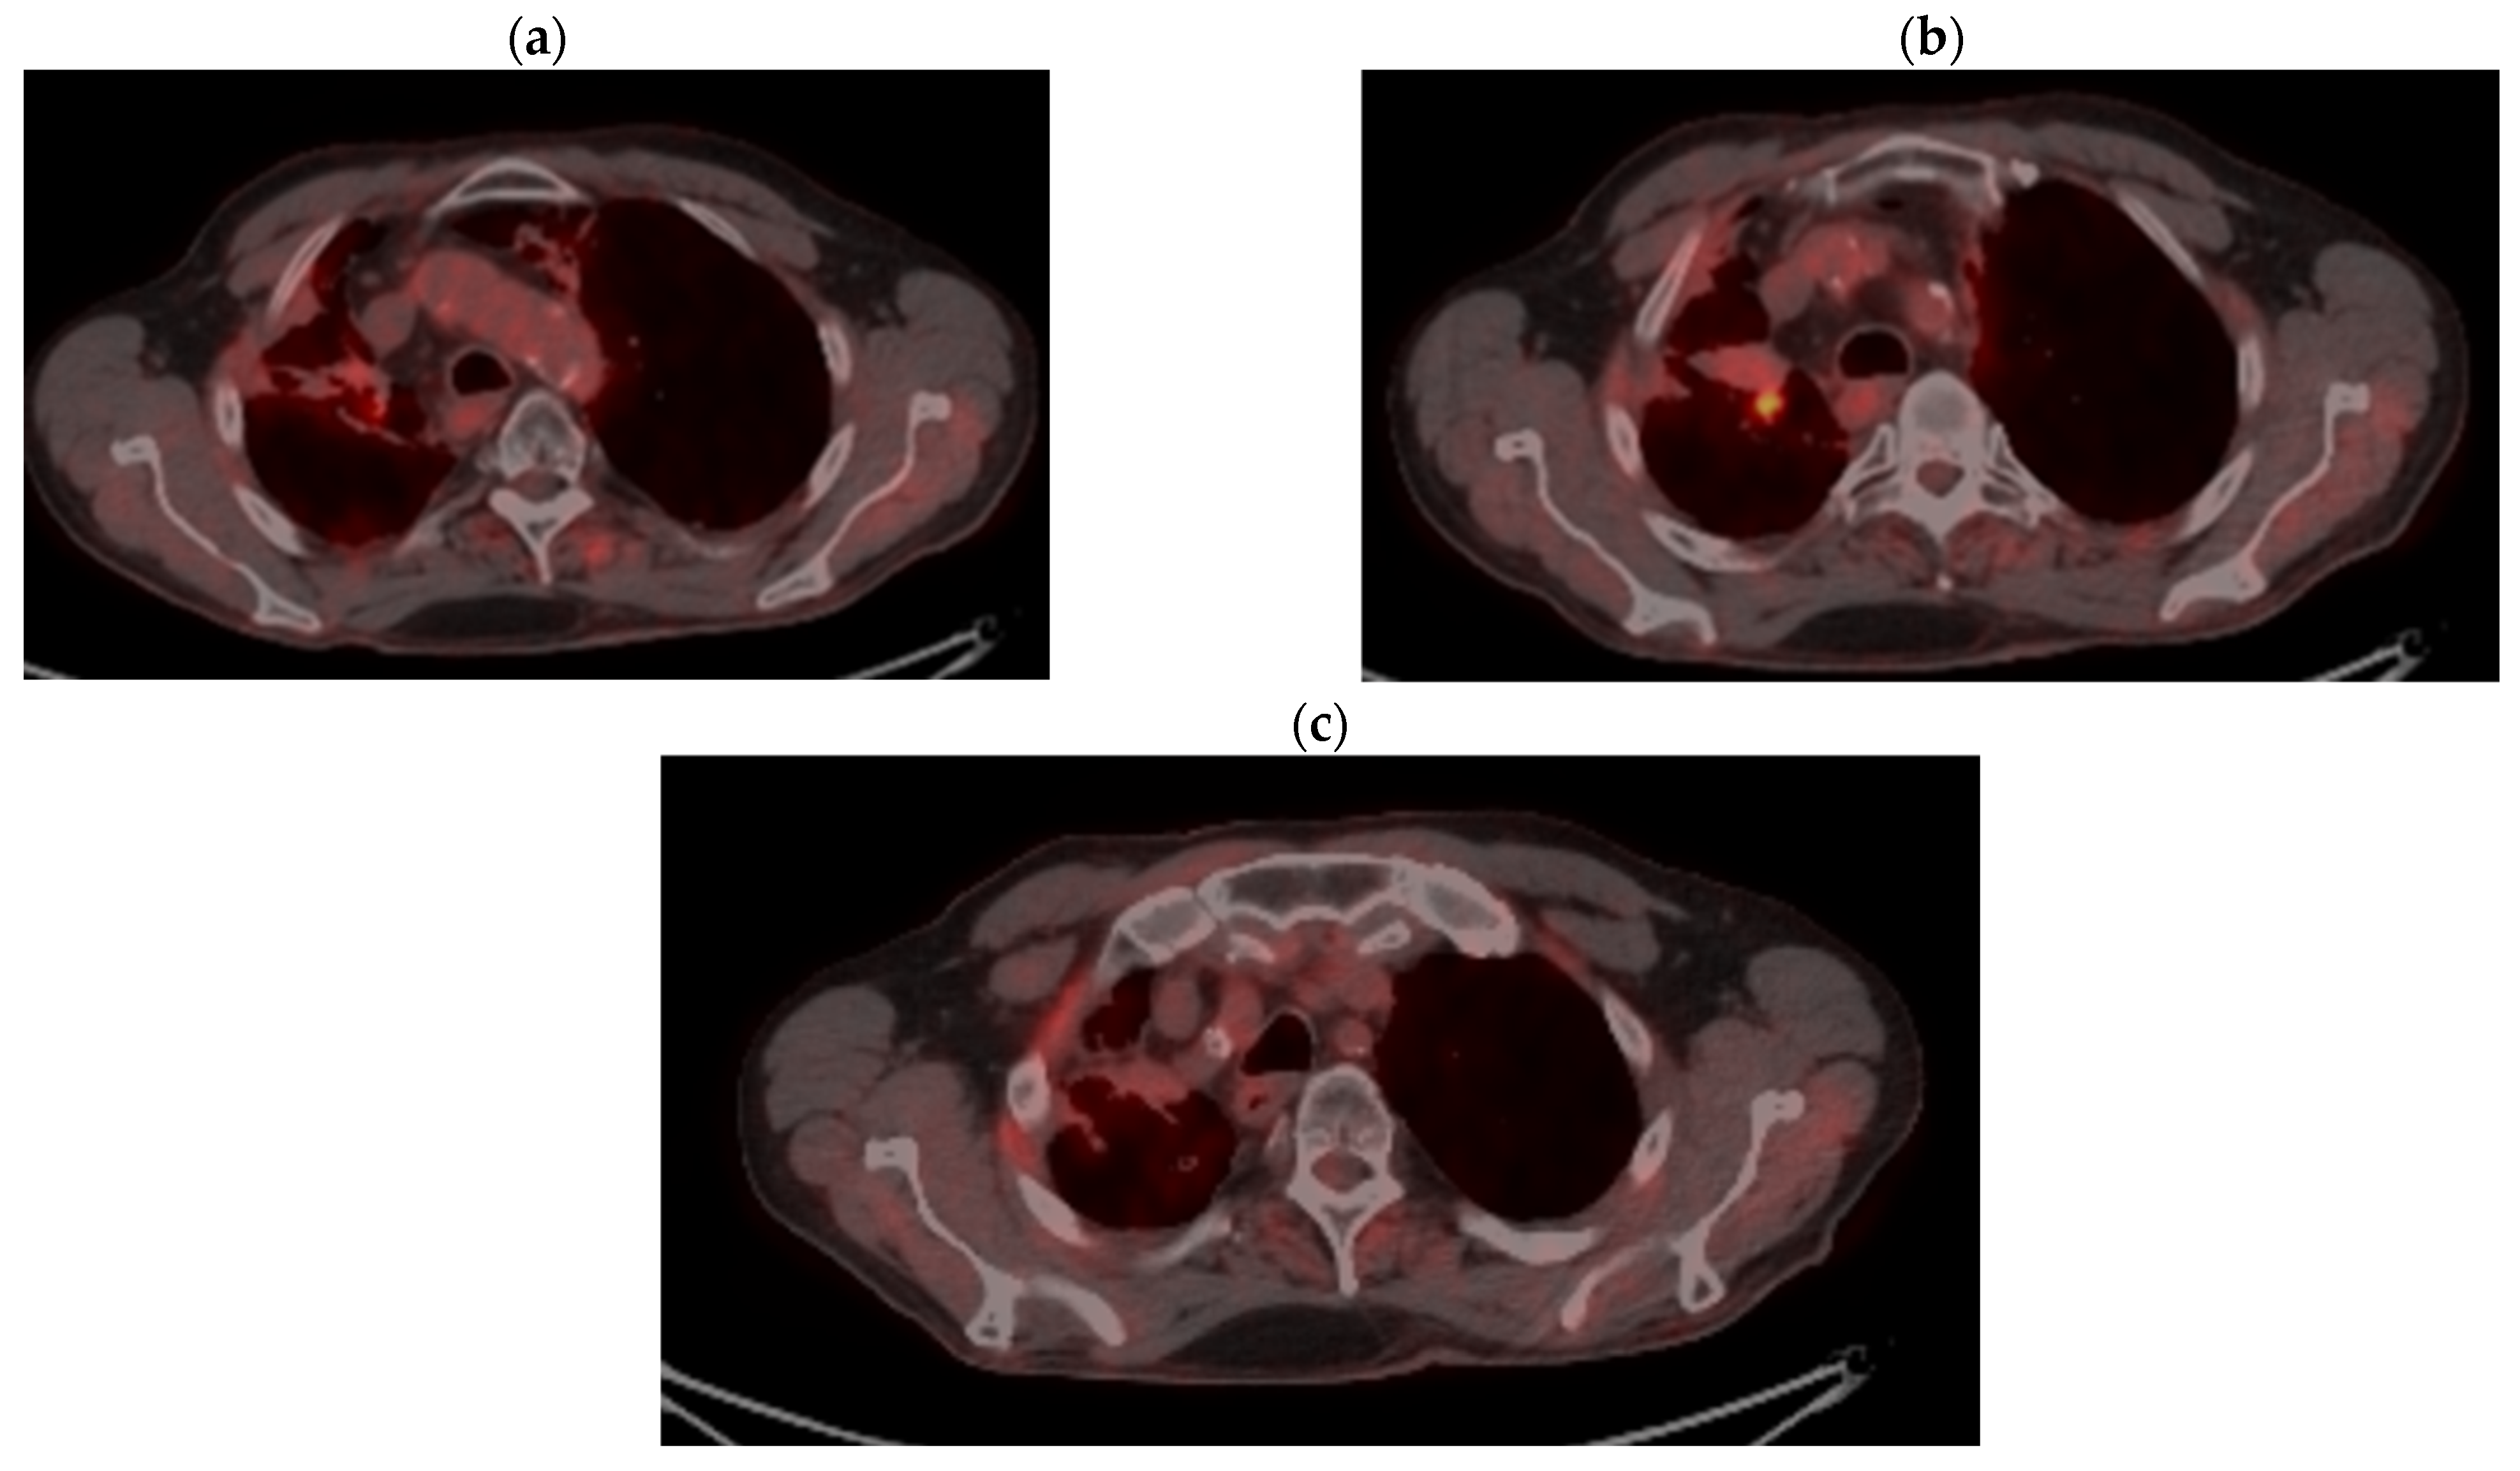

2.2. Monitoring 2022: Oncological Commission 1910/16.08.2022

2.3. Oncological Committee 07/25/2023 Recommended

- Consider rescue re-irradiation (SBRT), taking into account the current primary tumor dimensions of 24 × 34.2 mm on PET CT from 06/2023 and also the total dose previously administered (08–09/2020), the previously applied fractionation, the time between the two irradiations, the cellular repair time and the dose constraints for the organs at risk.